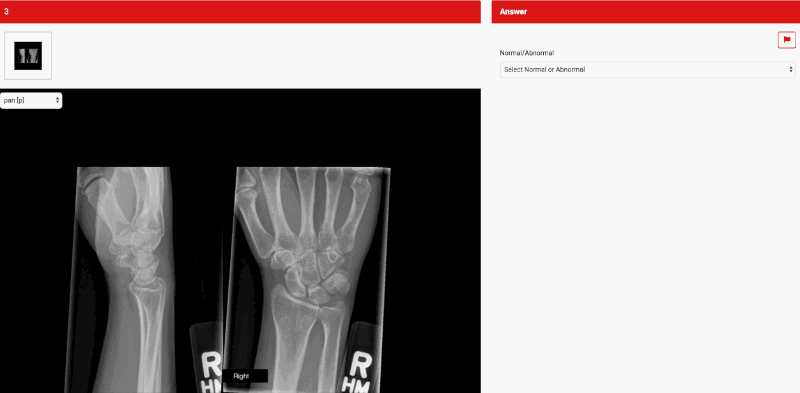

- Rapid Reporting:

You will get 30 images, each with one mark, so a maximum of 30 marks. The total time allotted is 35 minutes. One-third of these cases can be normal. Anatomical variants are considered normal. The rapid reporting component of the exam is marked out of 8.

- You have to report 30 cases (mostly radiographs) in 35 minutes. There will be a mix of normal and abnormal radiographs(40 to 60% each) and each pack will reflect an X-ray bundle from trauma referral.

- Images are digitized and displayed on OSIRIX workstation

- Normal or abnormal – if abnormal must write down a diagnosis

- Can write with a pencil or pen (both will be provided)

- There is only limited space for the answer, think before you write! (another good reason to use a pencil)

- Abbreviation ok to use – Rt (right), Lt (left), hash sign # (fracture)

- Can get 0.5 if the answer is incomplete

- Only ONE finding per film – if more than one usually related to the same mechanism (e.g. Rib fracture + lung contusion from trauma)

- Wrist radiograph checklist

- Triquetral fracture on lateral

- Scaphoid fracture will have 4 views

- Hamate hook # on lateral and AP

- Scapholunate dissociation

- Distal radius # – impacted fracture

- Buckle, torus, SH #

- AVN of lunate and scaphoid